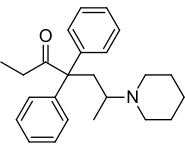

Open chain opioids

Amidones

- Dextromethadone

- Dipipanone

- Isomethadone=

- Levoisomethadone

- Levomethadone

- Methadone

- Methadone intermediate

- Normethadone

- Norpipanone

- Phenadoxone (heptazone)

Structures

| Amidones | ||||

|---|---|---|---|---|

|

|

|

Levoisomethadone Levoisomethadone | |

Noracetylmethadol Noracetylmethadol |

Levomethadone Levomethadone |

Methadone Methadone |

Methadone intermediate Methadone intermediate | |

Normethadone Normethadone |

Norpipanone Norpipanone |

Phenadoxone Phenadoxone |

Pipidone Pipidone | |